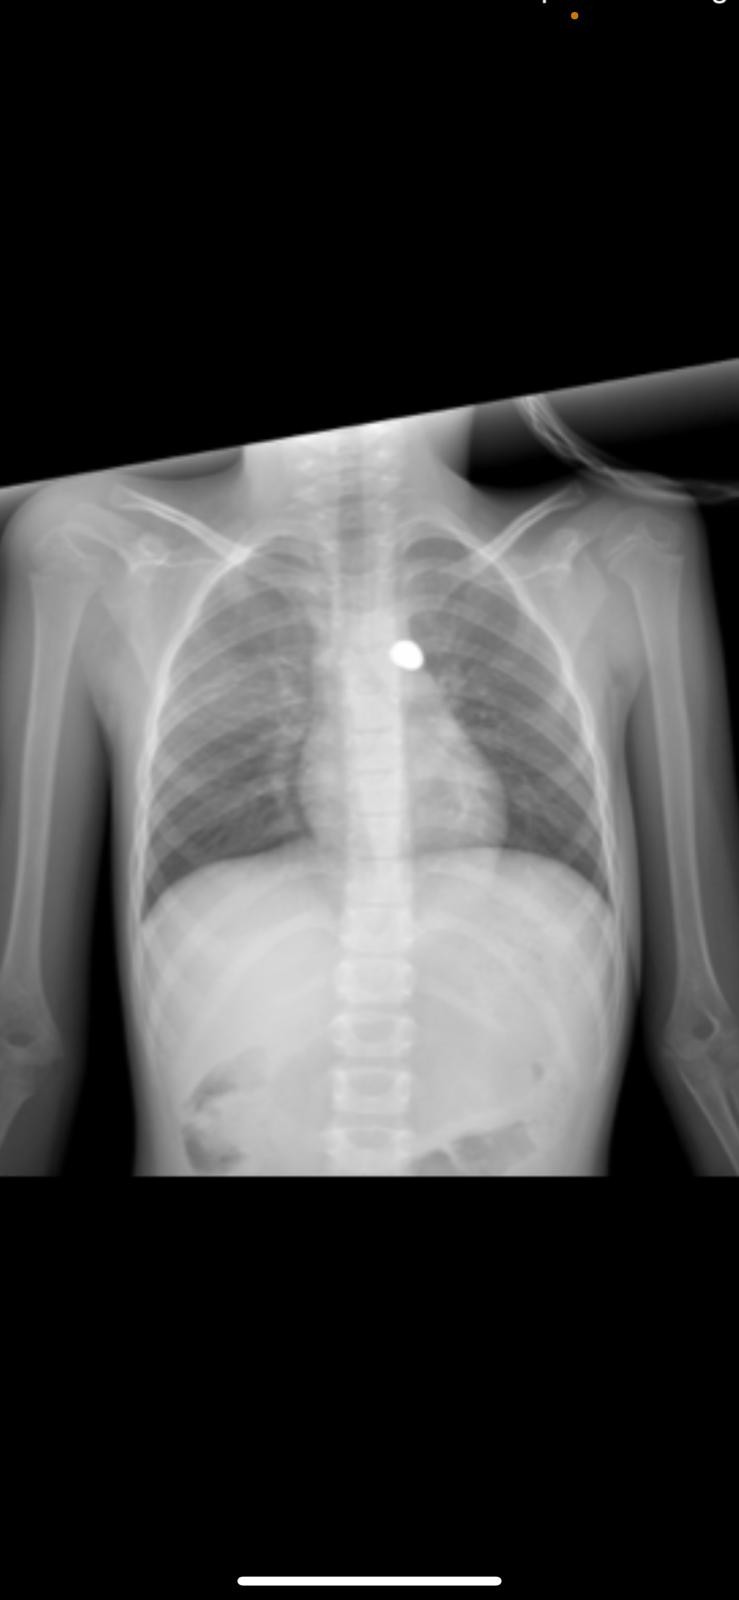

Adana’da 7 yaşındaki Yağmur sokakta oyun oynarken, husumetli iki aile arasında çıkan silahlı kavgada sırtına isabet eden kurşunla hastanelik oldu. Küçük Yağmur'un sırtındaki mermi çıkartılamadı.

Bu esnada sokakta oyun oynayan Yağmur Demir’in sırtına, iddiaya göre, Ramazan U.’nun tabancasından çıkan mermi isabet etti. Olayda Abdülkadir D. bıçakla Mesut D. ise sopa ile yaralandı.

Bu arada hastanede yapılan tedavilerin ardından Yağmur Demir hayati tehlikeyi atlattı. Ancak kız çocuğunun sırtından giren mermi sürekli hareket ettiği için alınamadı. Hastanede tedavisi devam eden kız çocuğunun vücudundaki merminin şimdi alınamayacağı hareketi durduğu zaman kontrol edilip ancak o zaman alınacağı öğrenildi.